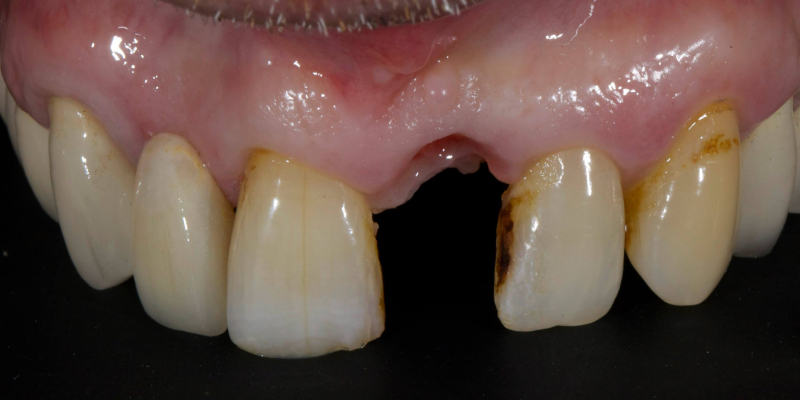

Here’s Elizabeth’s case. She had a periodontal lesion affecting the upper right central incisor (Fig. 13).

The tooth was extracted and a provisional nonprecious adhesive bridge with composite pontic was placed (Figs. 14-16).

The Rochette-type wing was placed on the lateral incisor abutment (Fig. 17). Grafting procedures were carried out before definitive restoration with a lithium disilicate adhesive bridge.